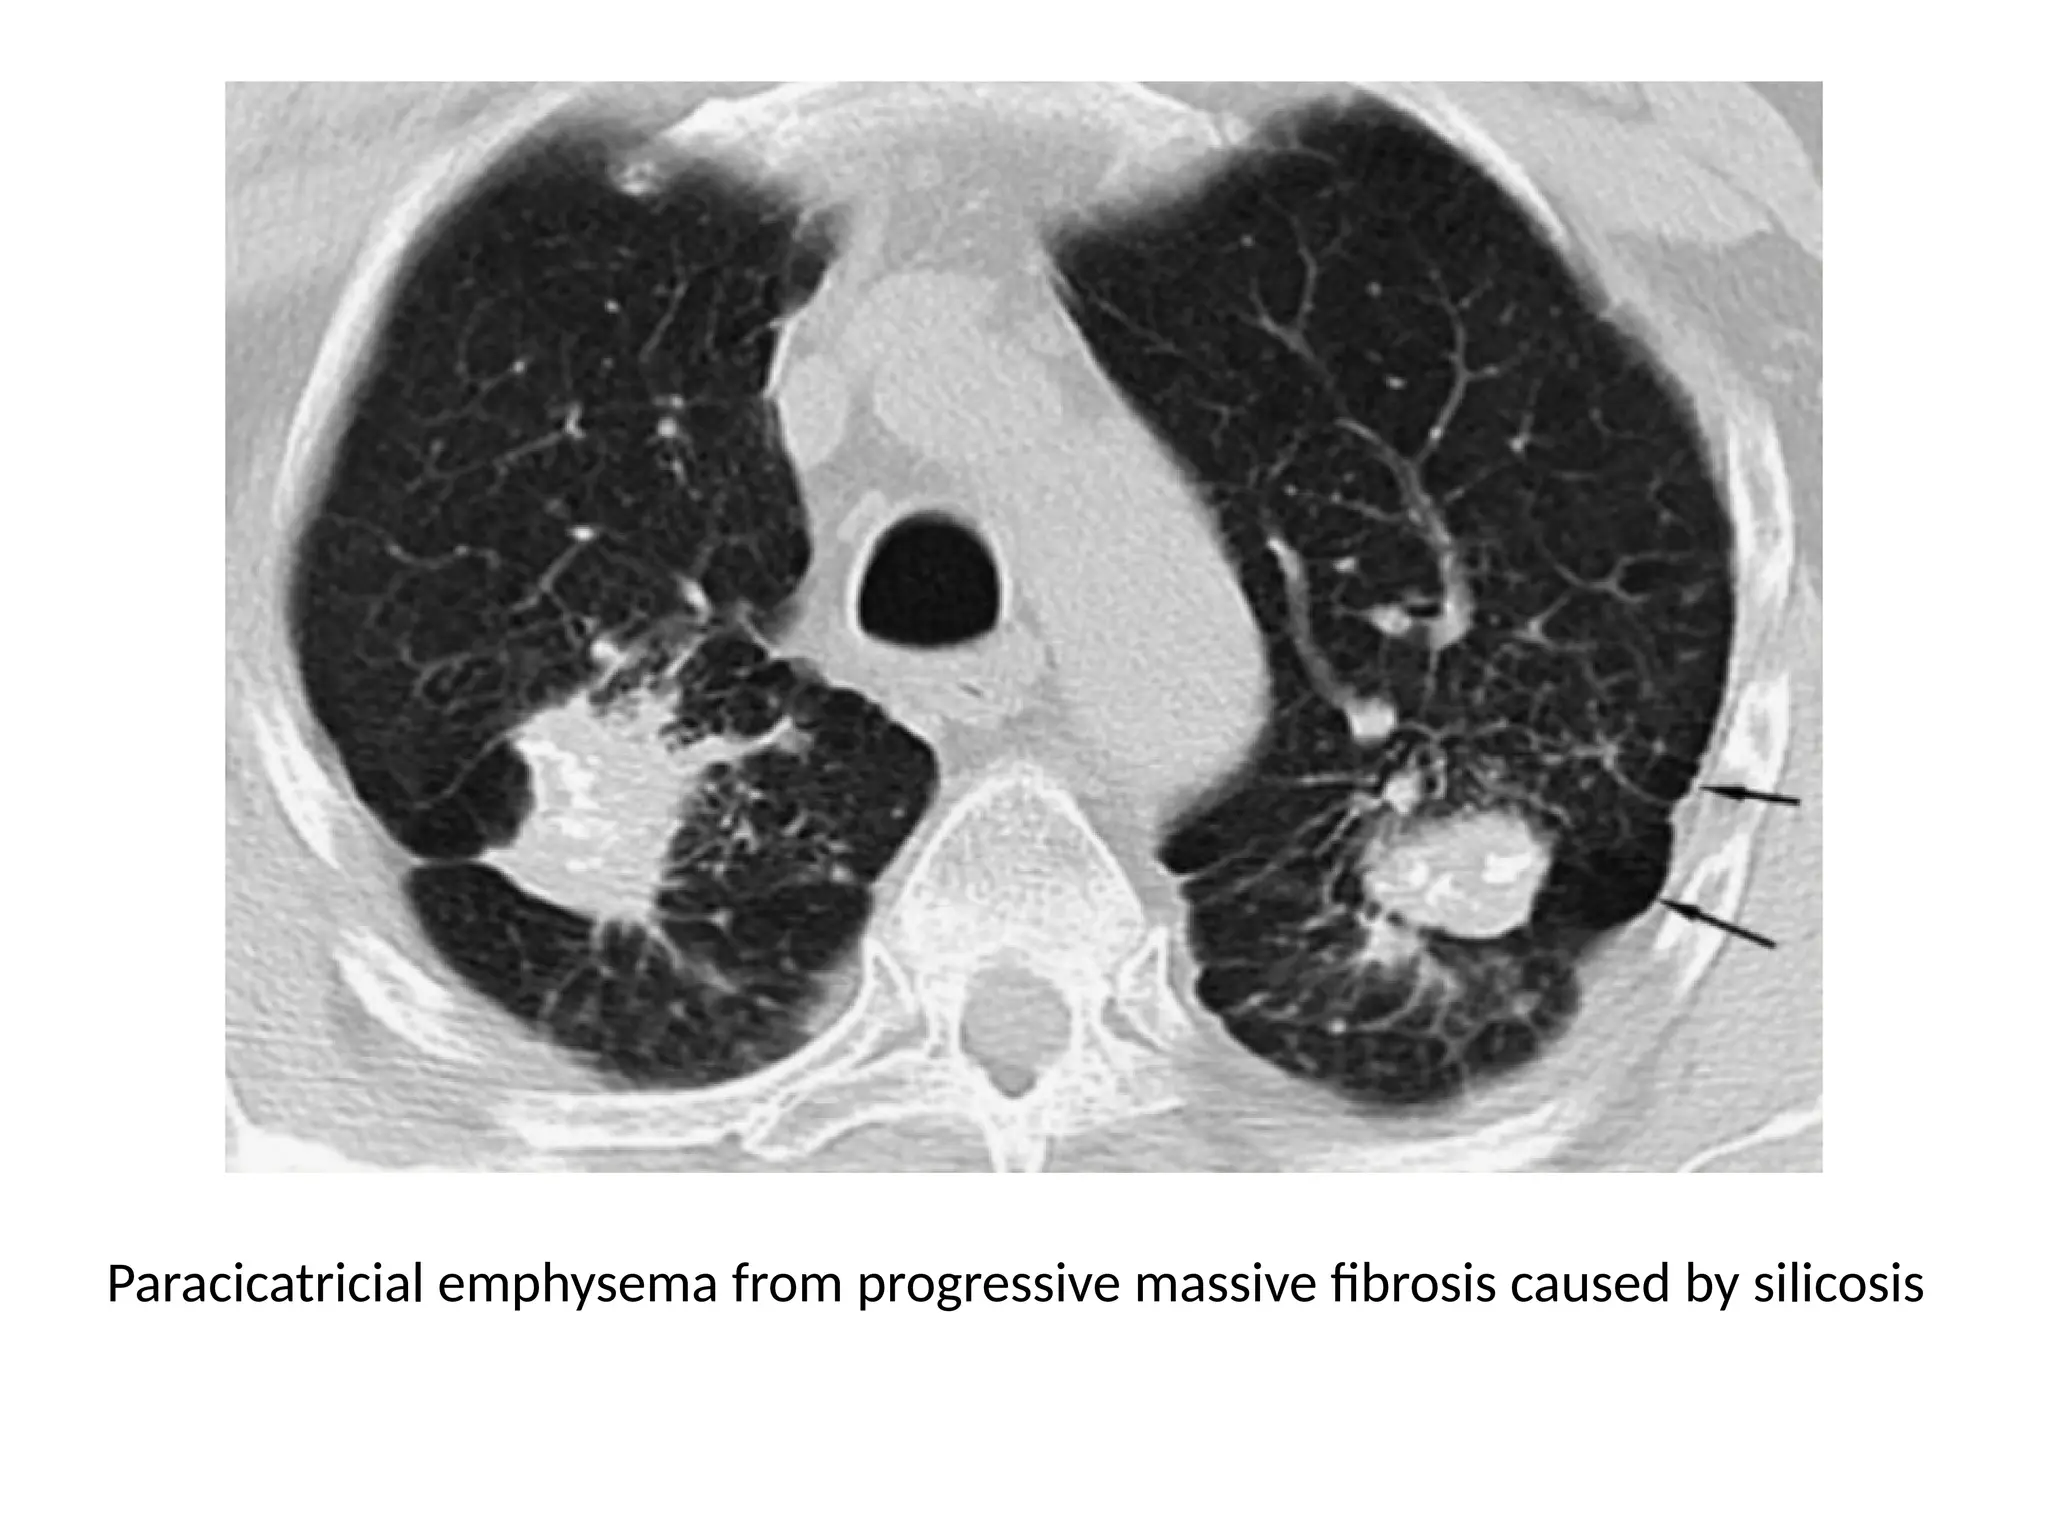

Paracicatricial emphysema from progressive massive fibrosis caused by silicosis

Emphysema • It ischaracterised by permanently enlarged airspaces distal to terminal bronchioles with destruction of alveolar walls • “without visible walls” • 4 types • Centrilobular - proximal respiratory bronchioles dilated, leaving normal distal alveolar ducts and sacs • Para-septal - enlarged airspace at the periphery of acini • Panlobular - uniform dilatation of the air space from the respiratory bronchioles to the alveoli • Para-cicatricial – air space enlargement adjacent to lung scarring

Paracicatricial emphysema fromprogressive massive fibrosis caused by silicosis